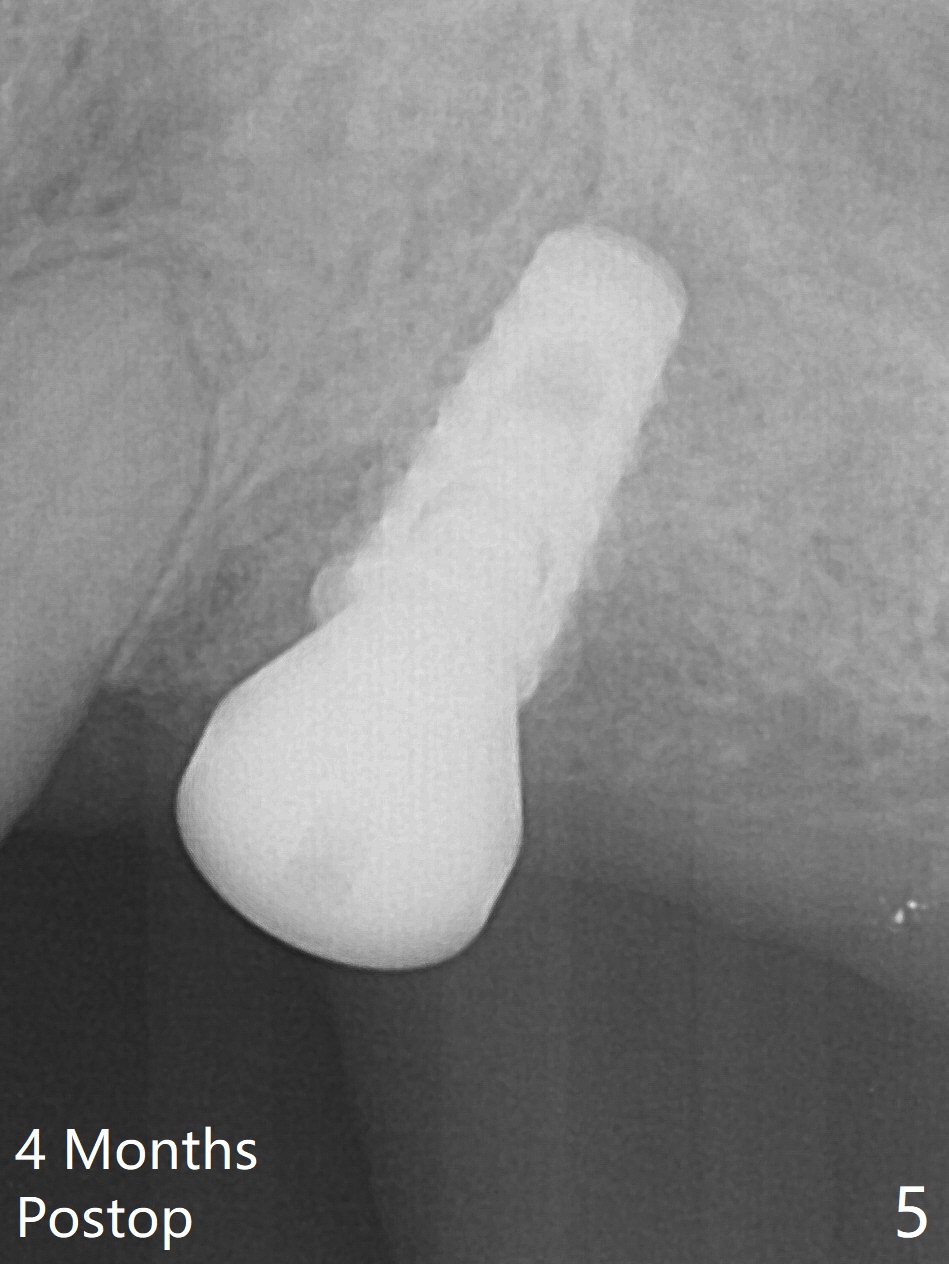

After extraction of the tooth #14 (Fig.1) and removal of granulation tissue associated with a distal fistula, a 1.6 mm drill is used to initiate osteotomy in the septum for 9 mm, followed by insertion of a 7 mm long parallel pin (Fig.2). The length of the subsequential osteotomy is 11 mm until 4.8 mm in diameter (overprep as will be shown below). The bone is hard so that sinus lift fails with 4.8 mm Magic Expander. Since a 5x9 mm dummy implant is placed with stability, a definitive implant with the same dimension is chosen with >50 Ncm (Fig.3,4). Prior to and after abutment placement, Vera graft is placed (*). The provisional perforates with loose abutment 3.5 months postop. A 6x4 mm healing abutment is placed. Osteointegration occurs 4 months postop (Fig.5,6).